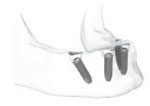

All-on-4 implants is the name of immediate function system whereby a fixed hybrid denture is secured onto 4 dental implant posts. 2 of the outer posterior implants is titled in order to anchor to anterior bone that tends to be more dense. If 5 implants is used, it is called All-on-5. If 6 implants is opted, it is known as All-on-6. If you use Straumann implants, their immediate function concept is known as ProArch.